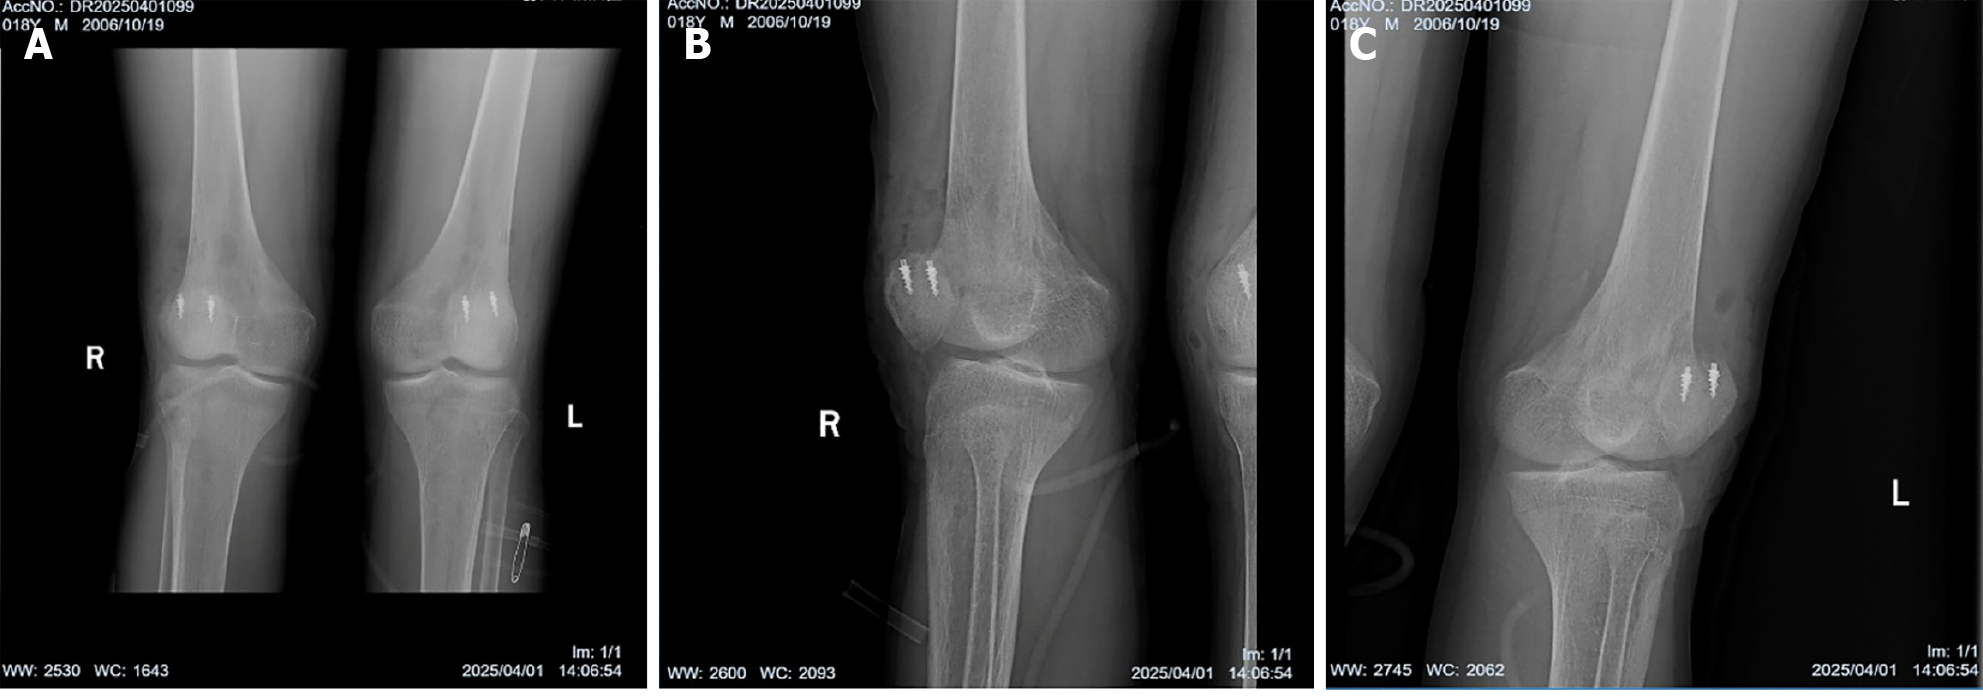

Figure 4 Plain radiography of bilateral knee joints after surgery.

A: Anteroposterior radiography of bilateral knee joints; B: Lateral radiography of right knee joint; C: Lateral radiography of left knee joint.